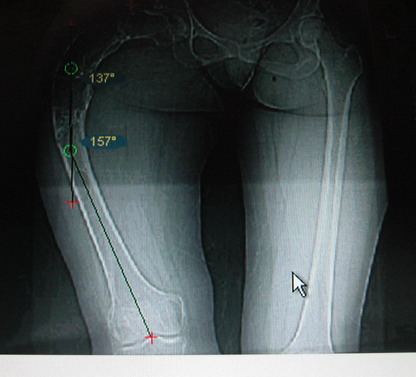

Моё мнение, что двойная остеотомия бедра с аппаратом Илизарова + Гексаподный механизм, или Тэйлора, В данной ситуации является методом выбора. Я очень извеняюсь за качество прилагаемых снимков, в которых я постарался отразить разницу междe одной и двумя остеотомиями бедра.

jo> отразить разницу межде одной и двумя остеотомиями бедра.

Скорее всего, второй уровень может оказаться нелишним лишь при переходе с аппарата на интрамедуллярный стержень. И его не поздно будет пересечь именно в момент введения гвоздя, если будет угроза перфорации стенки канала.